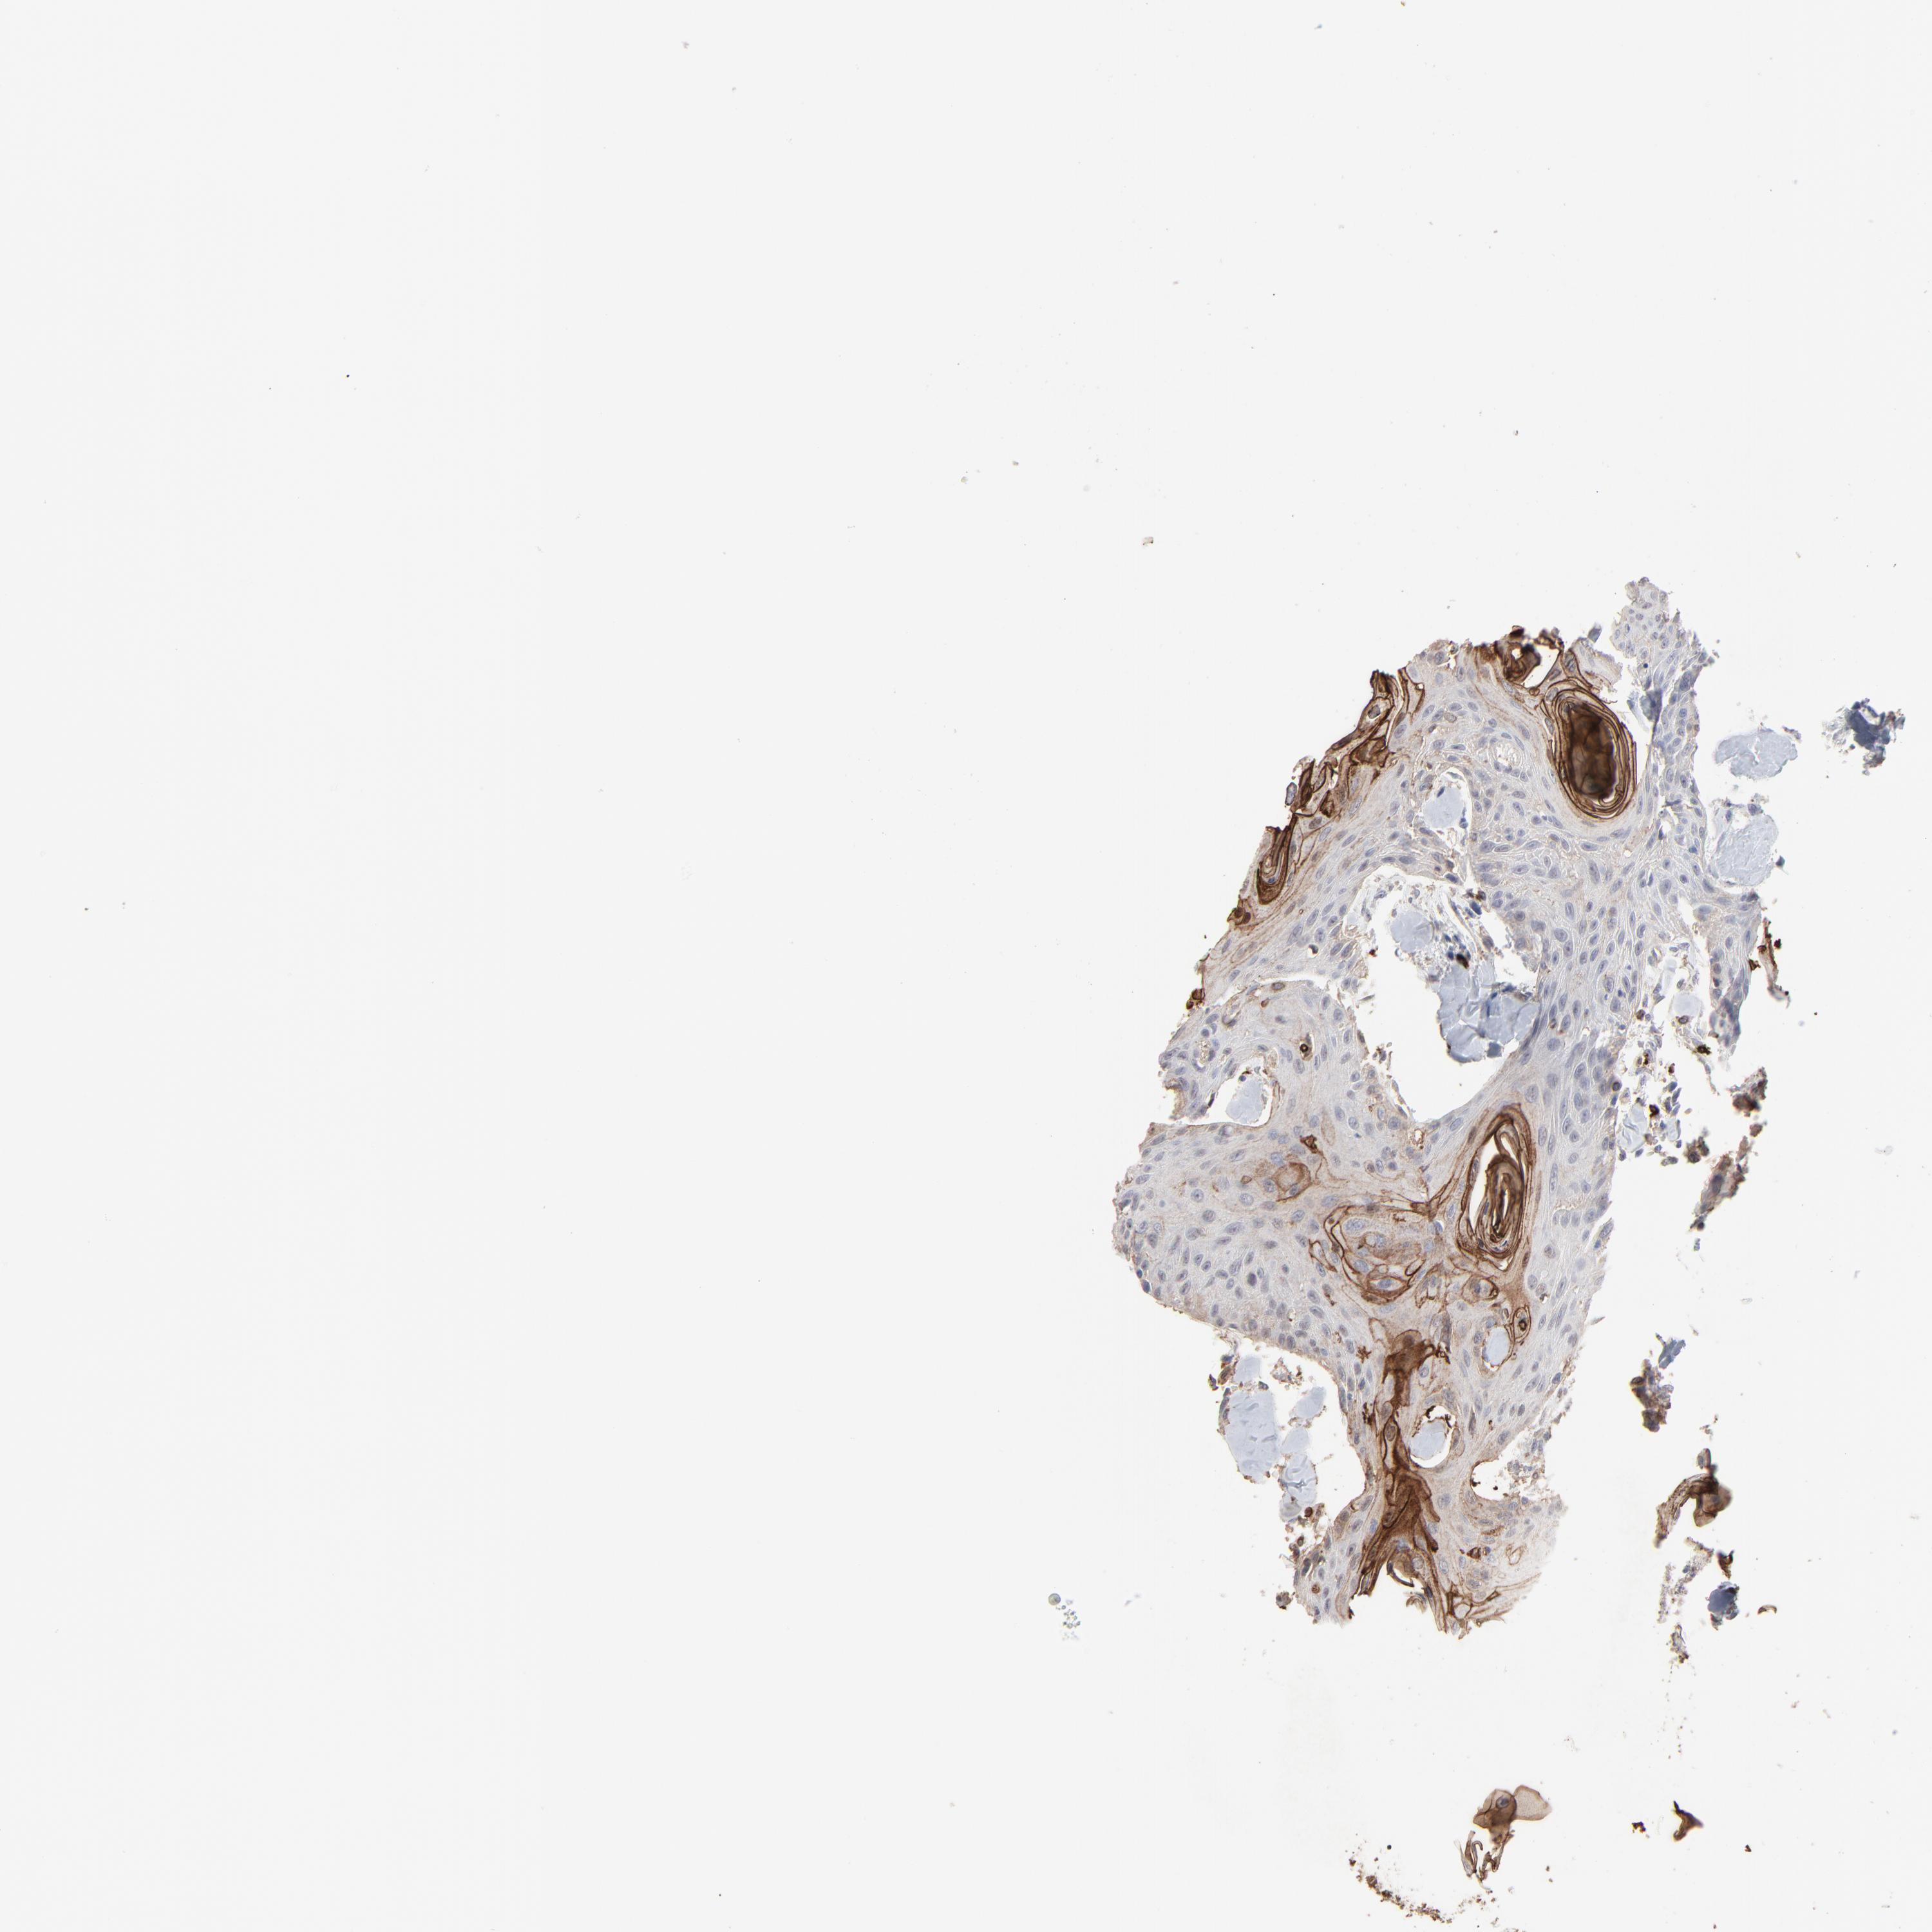

HEAD AND NECK CANCER - Protein expressioni

A mouse-over function shows sample information and annotation data. Click on an image to view it in a full screen mode. Samples can be filtered based on level of antibody staining by selecting one or several of the following categories: high, medium, low and not detected. The assay and annotation is described here.

Antibody stainingi

Antibody staining in the annotated cell types in the current human tissue is reported as not detected, low, medium, or high, based on conventional immunohistochemistry profiling in selected tissues. This score is based on the combination of the staining intensity and fraction of stained cells.

Each image is clickable and will lead to virtual microscopy that enables deeper exploration of all samples and also displays staining intensity scores, fraction scores and subcellular localization as well as patient and tissue information for each sample.

Antibody HPA003193

Staining

High

Medium

Low

Not detected

Intensity

Strong

Moderate

Weak

Negative

Quantity

>75%

75%-25%

<25%

None

Location

Nuclear

Cytoplasmic/membranous

Cytoplasmic/membranous,nuclear

Squamous cell carcinoma, NOS

Squamous cell carcinoma, metastatic, NOS